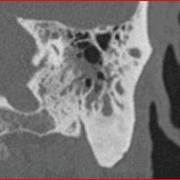

Case 1. An 81-year-old gentleman complained of intermittent ear drainage from the left ear for about 25 years. He has had myringotomy tubes for most of that time, reinserted periodically. Without the tube, he had ear pressure and hearing loss. With the tube, he had drainage that was occasionally purulent. Cultures showed E.coli, Klebsiella, and corynebacteria. Various courses of oral and topical antibiotics did not relieve the drainage. On physical exam, the left eardrum was dull, and there was a patent myringotomy tube with scanty purulent drainage. CT scan showed fluid in the mastoid cells and soft tissue in the attic without scutal erosion (Figure 1).

Figure 1